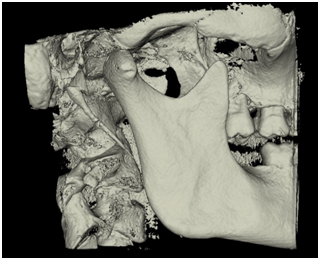

The morphology of SHC was recorded to evaluate the general structural appearance and the number of segments and was categorized into 3 types as single segment ossification, two segment ossification and three segment ossification (Figures 1‒3). The length was defined as the distance between the base of the SP and the tip of the ossified SHC. If there was segmental ossification of the SP, the distance was measured including the non-ossified parts (Figure 4). The antero posterior angle (APA) was defined as the angle made by the process with the perpendicular dropped from the lateral part of the external auditory meatus (Figure 5). The mediolateral angulation (MLA) was defined angle of intersection between the longitudinal axis of the SHC to the perpendicular dropped from the base of the process (Figure 6).

Figure 1 Shows single segment ossification.

Figure 2 Shows two segment ossification.

Figure 3 Shows three segment ossification.